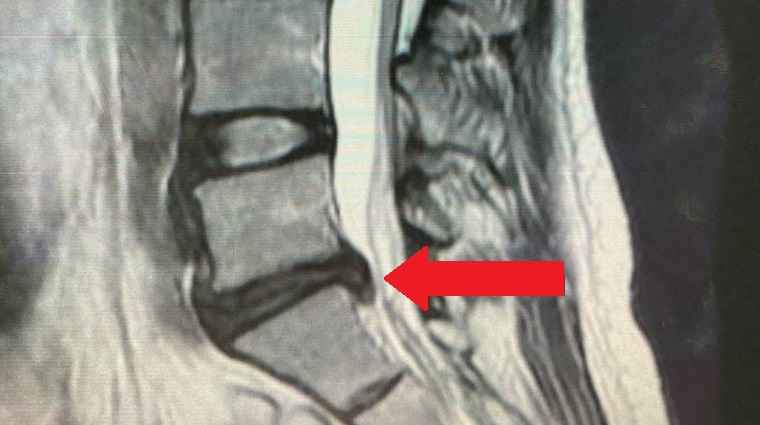

▲紅色箭頭處為MRI影像椎間盤突出位置。(圖/亞洲大學附屬醫院提供)

椎間盤位於2節脊椎骨之間,是連結每節脊椎的軟骨,能減緩脊椎的受力與衝擊。椎間盤突出多見於30歲至50歲的人,可分為退化與外力造成,前者因隨著年紀增長、姿勢不良,椎間盤的環狀韌帶會漸漸老化、軟化,導致椎間盤向外膨出;後者通常是因跌倒或搬重物造成突發性疼痛,使椎間盤破裂掉出。